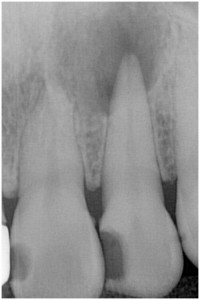

歯髄壊死 左下の小臼歯 川口の歯科 歯医者 さかえ歯科クリニック

2014年12月16日

術 後

術 前